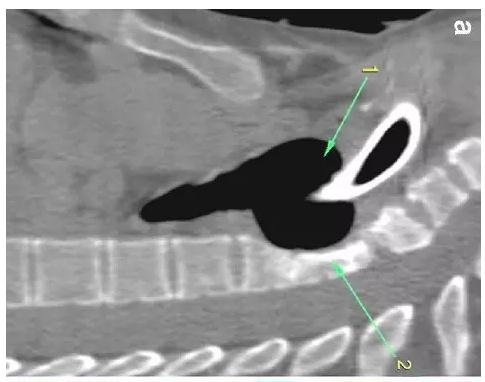

胸部CT顯示氣切套管氣囊周圍氣管擴(kuò)張,胸1-4椎體前部受到侵蝕(下圖a-c)。

下圖箭頭1為氣切套管氣囊緊貼T1-4椎體水平,造成椎體前部受到侵蝕(箭頭2):